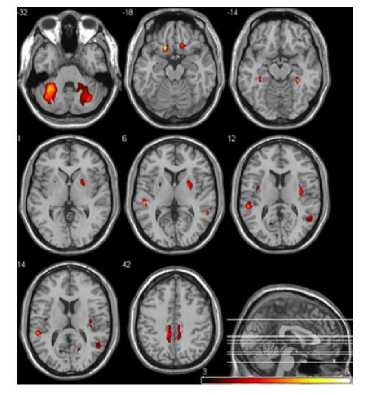

Abnormality in this region cause deficit in emotional responds and change in sexual behavior. Many pedophiles show lesions of the hippocampus and decrease in gray matter volume at the amygdala.

Decrease of matter result in an increased activation of the amygdala-hippocampal region during the presentation of images depicting prepubescent children but does not occur for imaging adults.[21]

In a very recent volumetric MR study a prominent total amygdala volume reduction as well as a local gray matter deficit in a group of pedophilic offenders was stated. Both reductions were significant on the right side, which corresponds to the somewhat more pronounced functional differences of the right amygdala.[23]

Figure 1. A Statistical Parametric Map Showing Significantly Decreased Gray matter Volumes in

Pedophile Patients Compared with Healthy Control.[23]